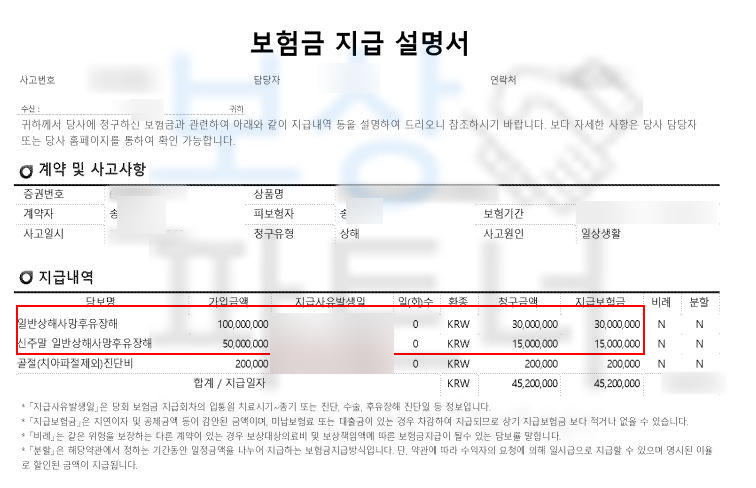

상해일반후유장해보험금 3,000만원

일반상해사망후유장해 보험금 3,000만원,

신주말 일반상해사망후유장해 보험금 1,500만원

각 보험사의 재해 및 후유장해 보험금 총 합

약 9,000만원 보상

이뤄냈습니다! 높은 지급율과 금액 때문에 보험사에서는 더욱 세세하게 문제삼았지만 보상파트너와 함께하여 구천만원의 후유장해보험금 받으셨습니다. 척추압박골절 후유장해 보험금 청구